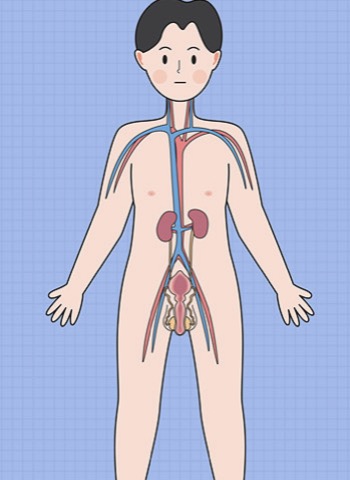

- 淋巴水肿:为什么会发生? 布骨康复医疗中心 ,2020-02-03

- 淋巴系统是由通道和淋巴结组成的网络,保证淋巴的循环和过滤。这种液体会将免疫细胞、营养物质和代谢废物排出体外。 淋巴水肿:为什么会发生? 淋巴水肿是一种与淋巴系统功能低下有关的疾病,它会阻塞或减慢淋巴循环。它可以在机体缺陷后自发发展,也可以在先天性疾病后发展,这种情况比较少见,称为原发性淋巴水肿。.....